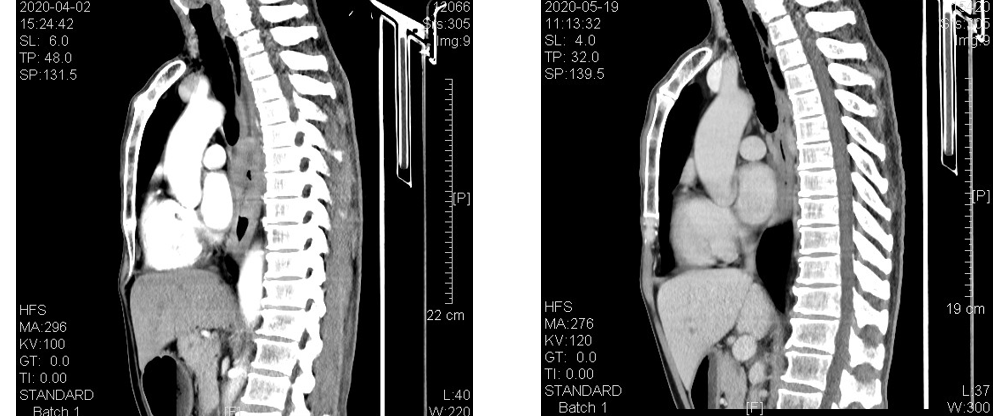

疗效对比(左:4月2日CT结果,右:5月19日CT结果):

食管CT(基线)示:胸中下段食管壁不规则增厚形成肿块,增强后见强化,最厚处约为1.7cm,长约13.4cm,上抵T4水平,下达T9下缘水平,病变段食管与降主动脉间的脂肪间隙消失,与其周长的接触面约为三分之一,向前压迫心包后缘,向左前紧贴左主支气管后壁,后壁略弧形受压改变,向右与奇静脉间的境界不清。

2020年4月2日钡透示:胸中段食管管腔狭窄,长约10cm,局部管壁僵硬,边缘及粘膜不规则破坏,对比剂通过缓慢,其上方管腔扩张明显。